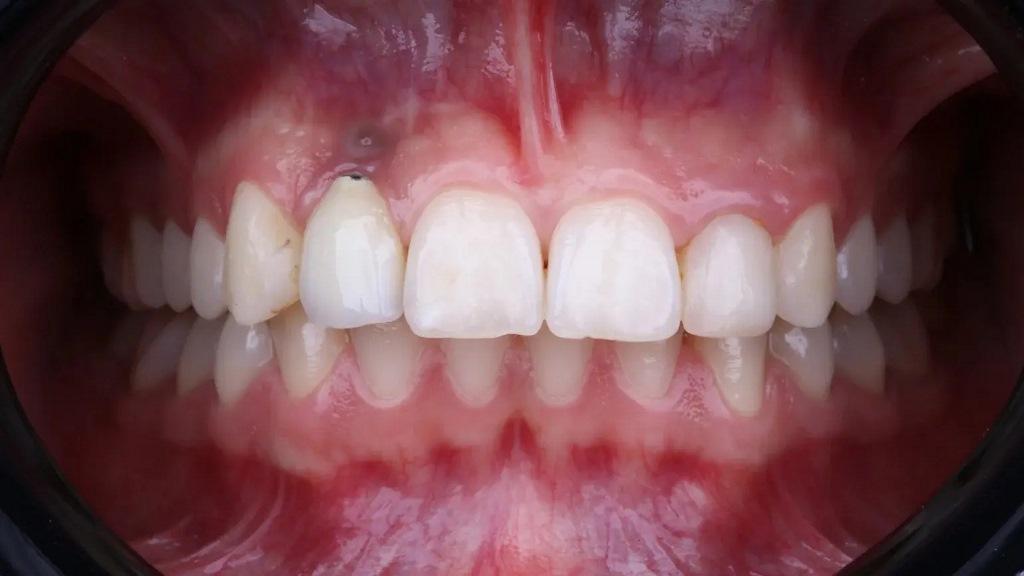

26-летнся пациентка с частичной адентией обратилась в клинику с эстетическими проблемами в области правого бокового резца верхней челюсти. Клиническое обследование выявило остеоинтегрированный, но неправильно расположенный имплантат. Мягкие ткани вокруг имплантата казались тонкими и воспаленными. Кроме того, сквозь десну было видно темно-сероватое обесцвечивание, называемое эффектом зонтика, вызванное потерей периимплантной кости и просвечиванием титанового имплантата (фото 1).

Фото 1: Воспаление слизистой оболочки вокруг имплантата (эффект зонтика), вызванное потерей костной массы и просвечивание титанового имплантата.